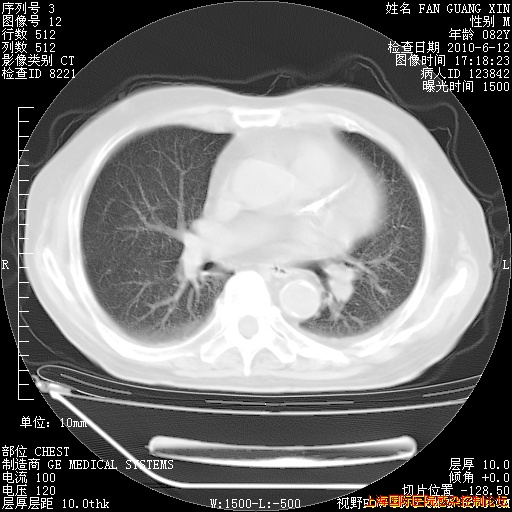

6月12日肺窗

整整相隔30天的肺部CT好像有所好转啊。甲强龙减量第3天,需要观察体温。